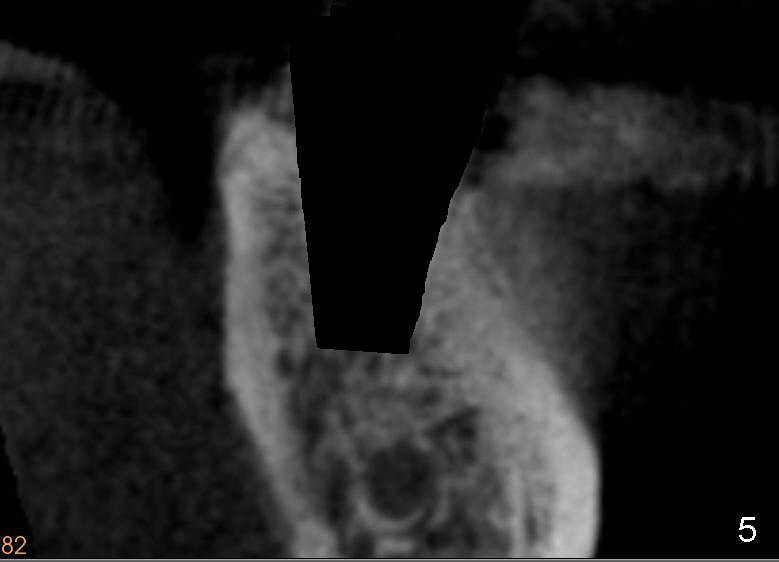

With planning and effort, the final osteotomy is in the middle of the socket (Fig.5). The implant is placed in restoratively favorable position (Fig.6).